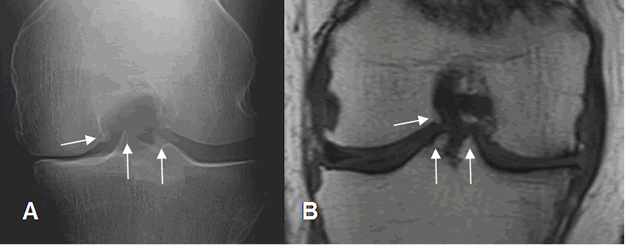

Fig 200. Osteofitos centrales.

A: Rx de túnel o proyección de Fick y B: RM coronal en T1. Presencia de osteofitos centrales,

que disminuyen la amplitud de la región intercondílea.